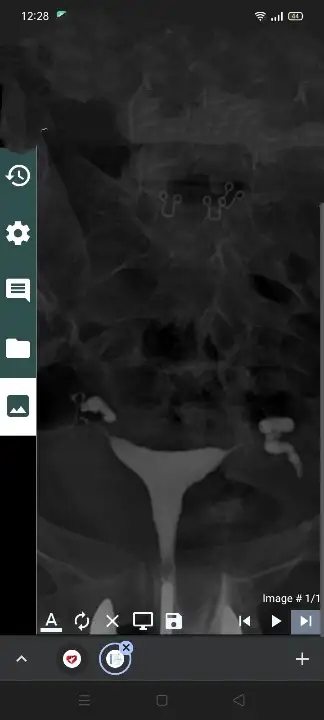

Buda görüntüler

Evet ilk cekilenlerde sağda geçiş yok ama burada tam gebeliği engelleyecek bir yapışıklık yok gayet iyi geçiş olmuş Canım